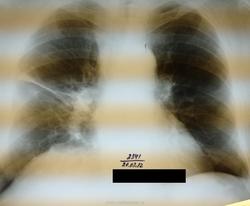

Пациент 75 лет поступил с клинической картиной правосторонеей пневмонии 20.02.12, по поводу чего лечился до 02.03.12 сейчас клиники пневмонии нет и готовят на выписку в удовлетворительном состоянии. А картина на контроле через две недели такая же. Возможно предположить наличие прямых или косвенных признаков центрального Neo правого легкого ?. Заранее спасибо!

ИМХО: справа в S3 было и сохраняется уплотнение лёгочной ткани перибронхиального харктера, которое с учётом клиники, можно раcценить как проявление пневмонии, которая в настоящий момент клинически разрешилась.Только вопрос какого характера пневмония -банальная или вторичная, параканкрозная остаётся открытым.Показана РКТ ( если недоступна, то как суррагат последней  срединная линейная томография, на проходимость бронхов) + бронхоскопия. Я бы ещё постарался поднять ФЛО-архив- не нравится низкое расположение малой междолевой плевры в медиальном отделе, за счёт чего это произошло?- уменьшение в объёме средней доли? ( если-да, то когда это возникло сейчас или давно?) или вздутие S3? Если ничего не сделают и выпишут пациента, то в случае варианта, что пневмония была на фоне нарушения проходимости бронха опухолевого генеза, следут ожидать скорого рецидива пневмонии.

Просто, возможно я ошибаюсь, скорее врего ошибаюсь, но я не вижу на представленных изображениях ни скиалогических признаков пневмонии, ни скиалогических (прямых, или косвенных) признаков центрального рака.

И, у меня возникает законный вопрос, о том, какую пневмонию лечили?

Скорее всего реакция плевры. Я считаю, что динамика есть, при чем положительная.(?)

Согласен, это не сильно выражено, но тяж как будто стал аккуратнее, легочной рисунок чище.